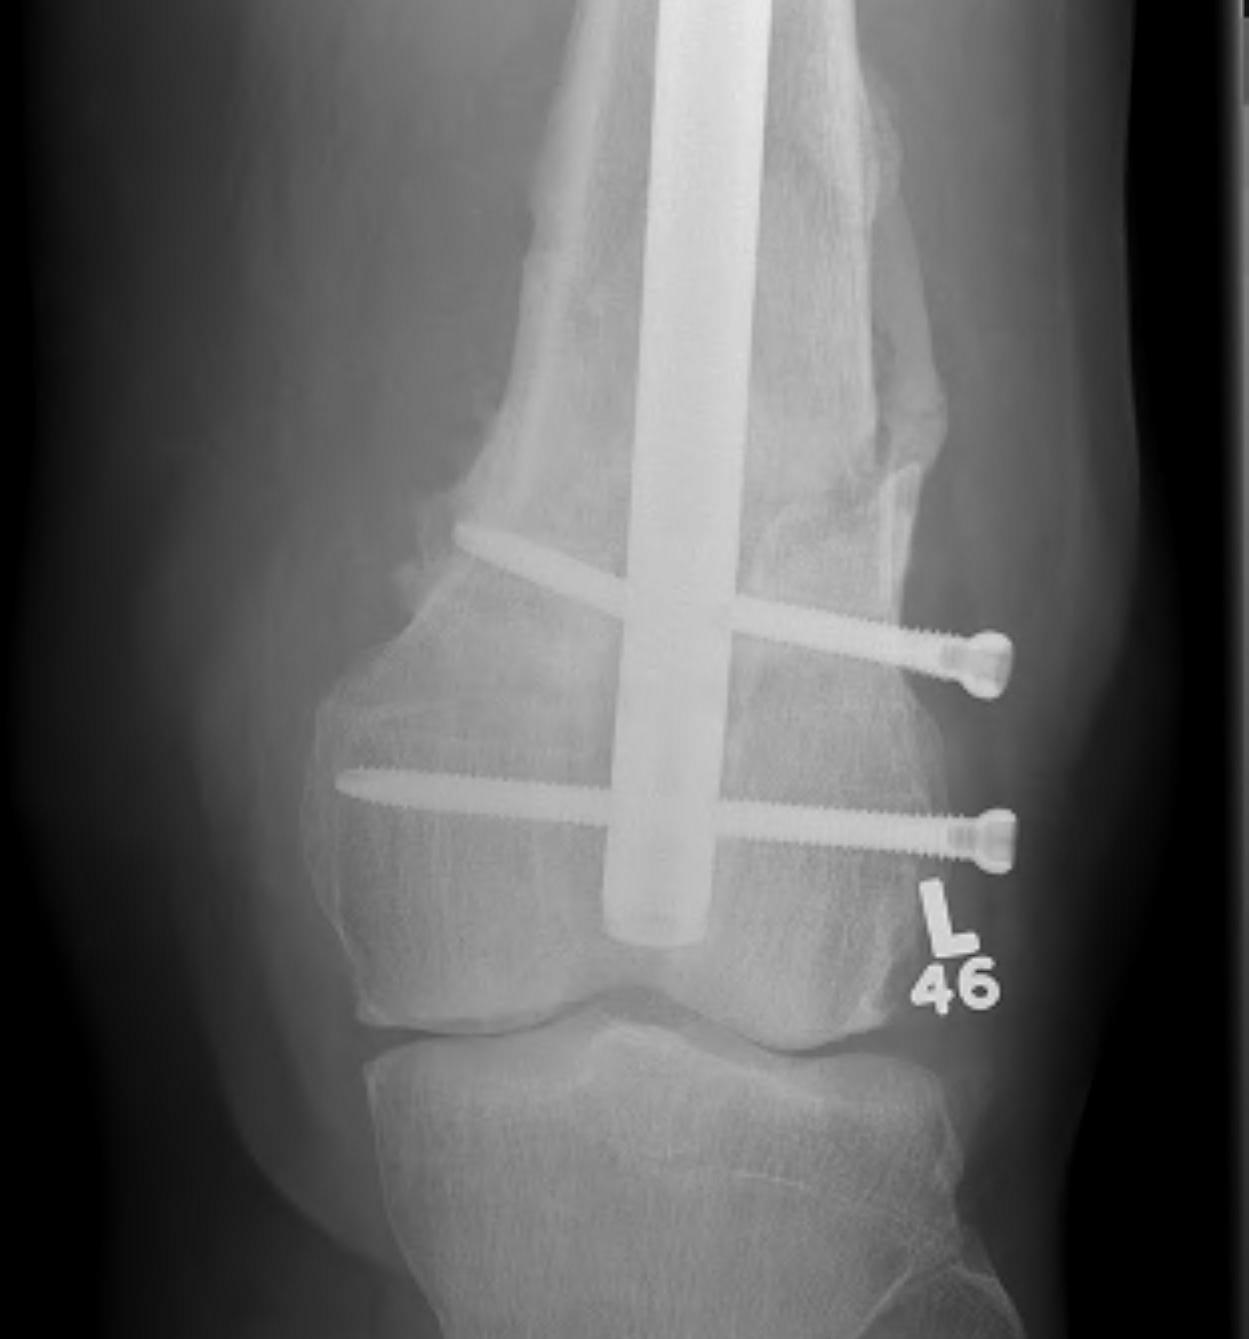

Type C: Complete articular

Xray / CT

Options

Dual Plate

Plate + Retrograde nail

Distal femur replacement

Indications

Significant comminution

Loss of medial cortical buttress

Results

- 21 comminuted distal femur fractures

- increased union rates with double v single plate

- increased revision rate with single plate